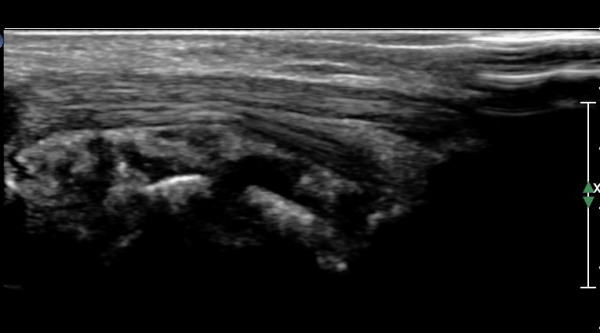

¹ß¸ñ ¿ÜÃø Ⱦ´Ü¸é(ºñ°ñ°Ç Ⱦ´Ü¸é)°Ë»ç¿¡¼­ ºñ°ñ°Ç ½ÉÃþÀÇ ´Ù·®ÀÇ ¼ö¾×Àú·ù°¡ °üÂûµÈ´Ù

(»çÁø 5, 6).